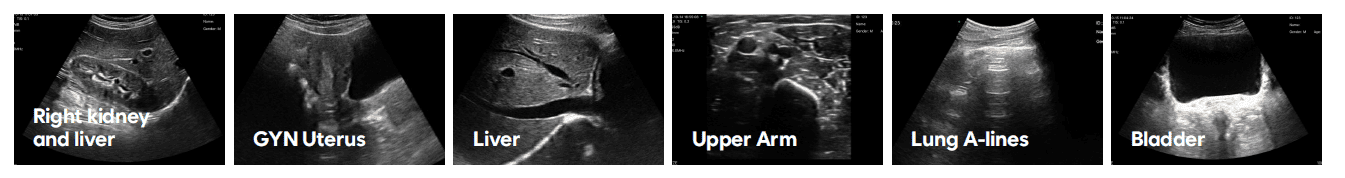

Klinické využití

SonoMe je navržen pro rychlou orientační i cílenou diagnostiku v různých oborech:

- urgentní medicína a intenzivní péče

- interní medicína a praktické lékařství

- gynekologie a porodnictví

- urologie

- ortopedie a sportovní medicína

- anesteziologie (navigace při výkonech)

- estetická medicína

- péče o seniory a domácí péče

Přístroj umožňuje například rychlé posouzení vnitřního krvácení, vyšetření plic, močového měchýře, cév nebo navigaci při punkcích a injekčních zákrocích.